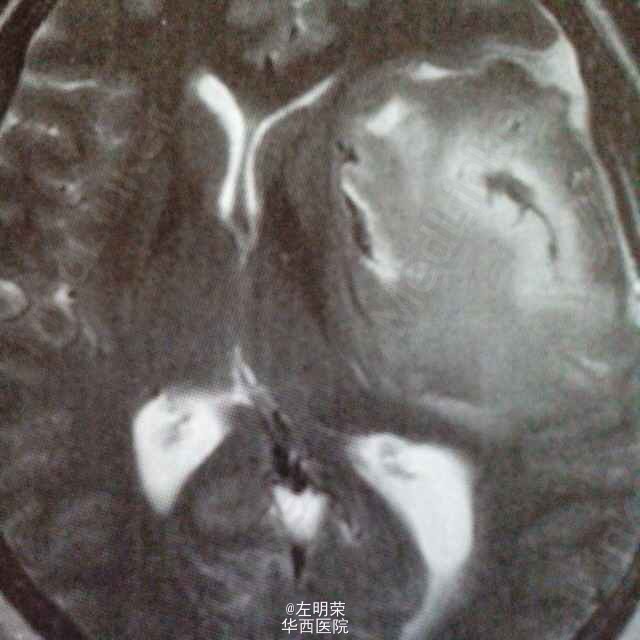

52岁女,吐字不清2年,加重伴间断头胀1个月。根据MRI特点考虑表皮样囊肿。手术切除病灶,肿瘤有包膜,囊内也豆渣样物,质软。病理示:表皮样囊肿